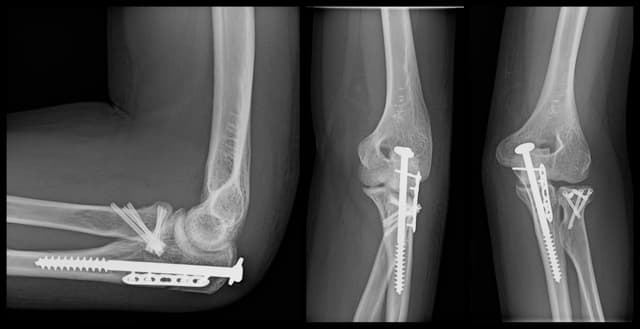

Imaging

Post-op